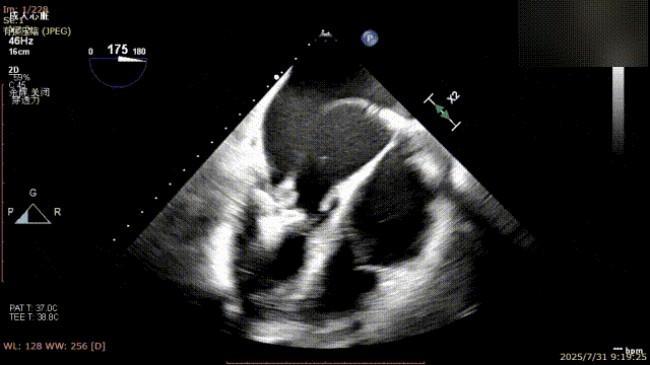

手术过程中,麻醉与围术期医学科副主任医师马金本确保麻醉过程平稳。心脏大血管外科主治医师董明亮穿刺股静脉置入血管鞘,并在心脏超声科梁皓主任及段福建教授TEE引导下,顺利穿刺房间隔,房间隔穿刺高度4.9cm。随后,在王安彪主任以及刘洋教授指导、心脏超声科梁皓主任TEE引导下,董明亮医师沿输送系统将延展呈“一字型”状态的国产夹合器送至左房,缓慢关闭夹合器并进行弹道测试。调整夹合器位置和方向后,董明亮医师再次将夹合器延展呈“一字型”完成跨瓣,避免发生腱索缠绕,成功捕获瓣叶后关闭夹合器,二尖瓣反流显著下降。夹合器完全解离后,超声示二尖瓣反流程度显著下降,残余反流0,平均跨瓣压差1mmHg,手术圆满成功。

夹合器“一字型”状态进入左房

缓慢关闭夹合器